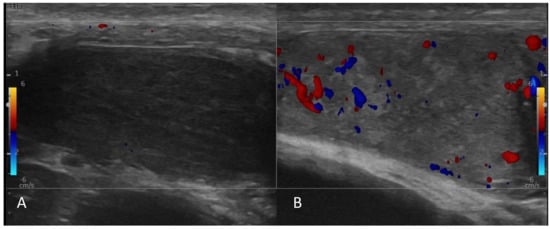

- A case of a patient with AIP type 1 and other organ involvement (bile ducts, testicles, nasal polyps, and lungs) is described.